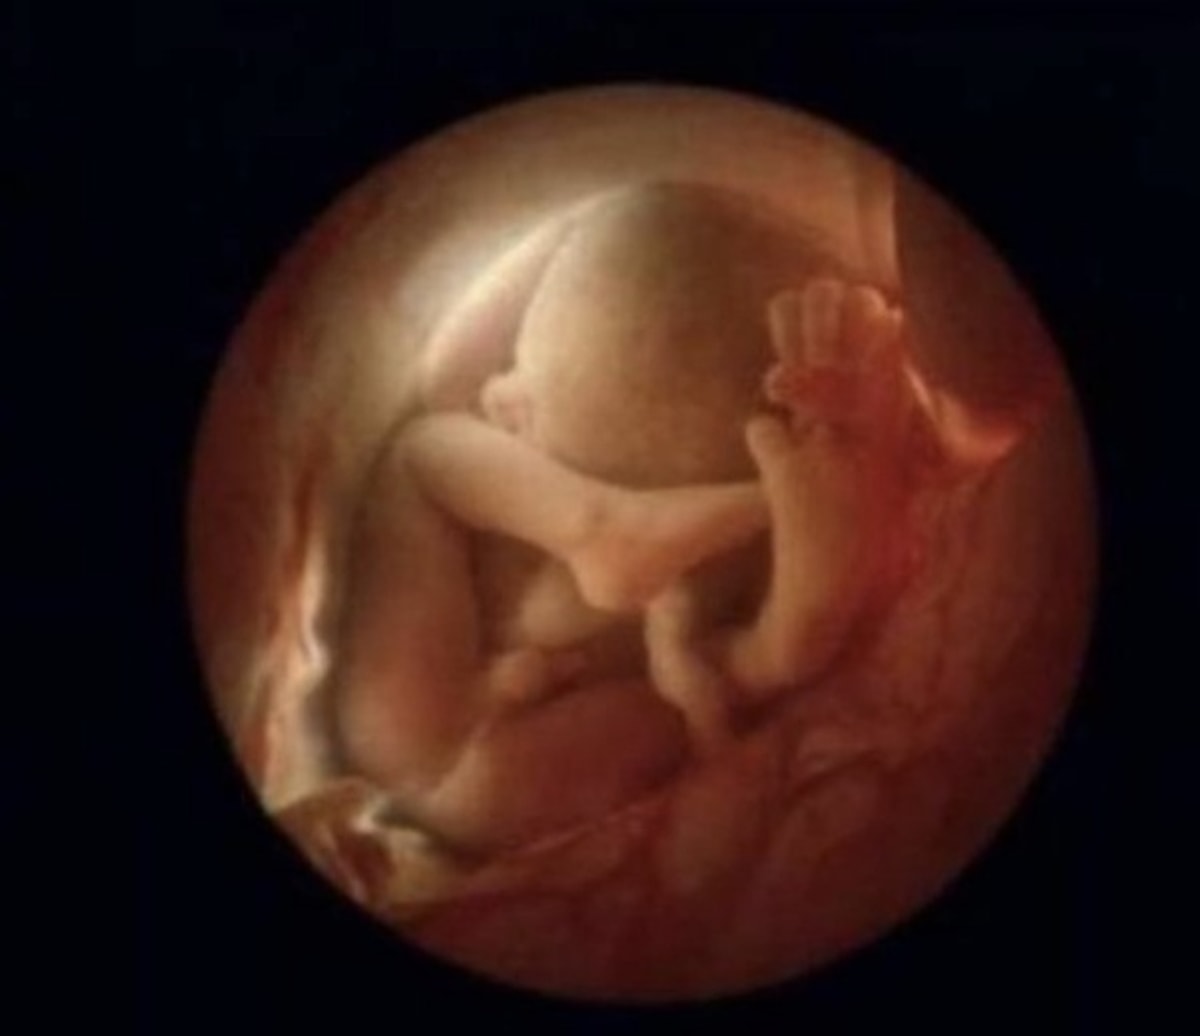

37 недель видео

37 недель видео 99 фото